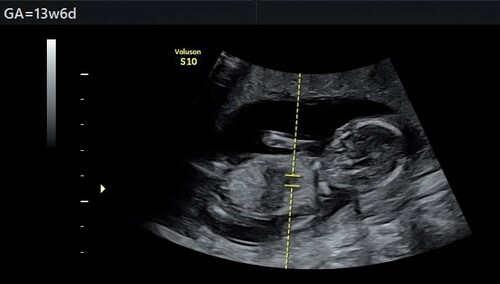

Hi allemaal! Vandaag de 13 weken echo gehad en ik ben heel benieuwd of jullie hier iets in kunnen zien? 😍

Is over deze echo iets te zeggen op basis van de nub-theorie?😊

Vandaag een tussenecho gehad, als overbrugging naar de geslachtsecho op 13 maart. Het is een long shot… (en de baby ligt ook nog eens op z’n kop), maar kan iemand hier wijs uit worden? :-)